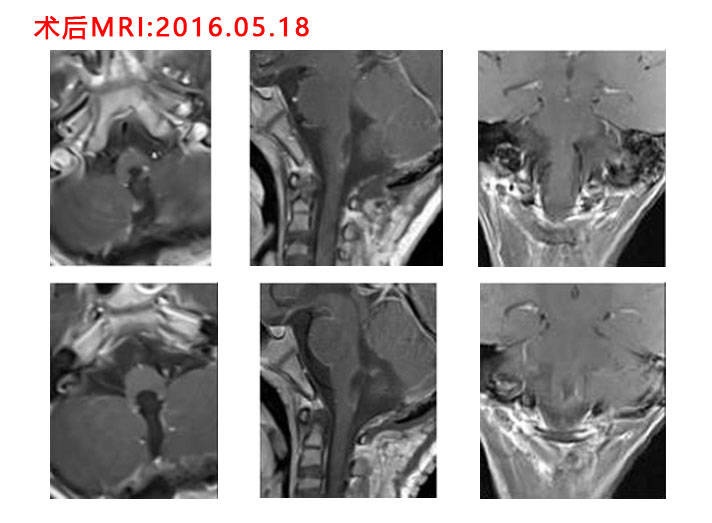

5岁小患者脑干恶性室管膜瘤切除术

图片尺寸712x523